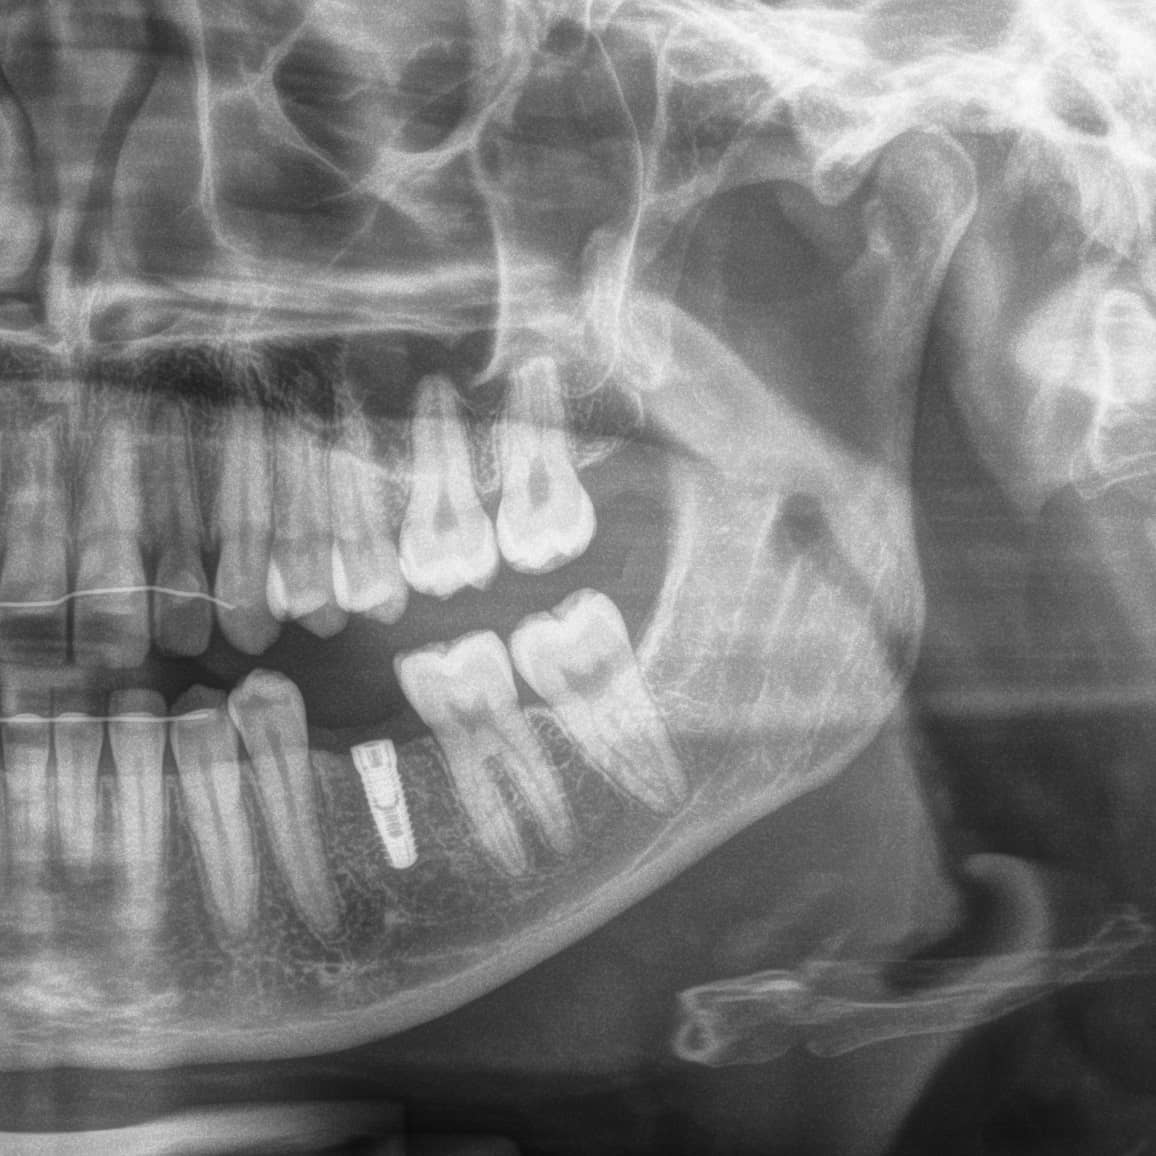

Implantate sind mittlerweile in aller Munde. Im Prinzip handelt es sich hierbei um künstliche Zahnwurzeln. Es sind Schrauben aus Titan oder mittlerweile auch Keramik, die in einer kleinen Operation in den Kiefer gesetzt werden, wo sie mit dem Knochen verwachsen. Sind die Implantate osseointegriert (eingeheilt), können darauf Kronen oder Brücken verschraubt werden und der fehlende Zahn ist wieder festsitzend ersetzt.